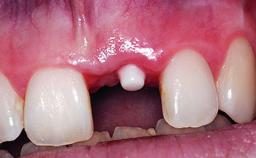

Replacement of an Upper Right Central Incisor with Root Resorption: Ridge Preservation, Delayed Placement of an NC Bone Level Roxolid Implant

A 32-year-old female Caucasian patient with a compromised maxillary right central incisor was referred to us by a general dentist. Her chief complaints were discomfort and mobility of tooth 11 with unsatisfactory esthetics due to discoloration. The patient reported a previous trauma, some years earlier, as the origin of pathology on the afflicted tooth. Anamnesis was negative for any other dental or periodontal pathology in the remaining dentition. The patient did not take any medication and reported to be a light smoker (5–10 cigs/day). She had high esthetic expectations of her treatment. The extraoral examination revealed a high smile line with full exposure of her maxillary teeth and surrounding soft tissue in the area between the second premolars.